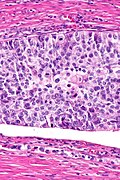

Images

PROSTATE TISSUE, TRANSURETHRAL RESECTION:

- HIGH-GRADE UROTHELIAL CARCINOMA WITH FOCAL STROMAL INVASION, AND EXTENSIVE

INTRADUCTAL SPREAD IN FRAGMENTS WITH BENIGN PROSTATIC GLANDS.